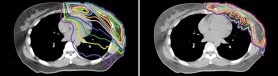

La radioterapia en toda la mama o en la pared torácica y en los ganglios linfáticos mamarios internos puede administrar una dosis de radiación al corazón que aumenta el riesgo de eventos cardiovasculares. Para ver si la terapia de protones puede reducir este riesgo, un ensayo clínico multiinstitucional está comparando la terapia de protones con la radioterapia basada en fotones estándar para pacientes con cáncer de mama localmente avanzado.

La Dra. Hoffman es la investigadora principal del MD Anderson en el ensayo RAD-COMP en fase III (N.º 2016-0085), que está inscribiendo a pacientes con cáncer de mama con afectación ganglionar que se han sometido a mastectomía o lumpectomía y requieren radioterapia de toda la mama o de la pared torácica y los ganglios linfáticos mamarios internos. “La irradiación de la cadena ganglionar mamaria interna conlleva un alto riesgo de cardiotoxicidad, porque la cadena se extiende precisamente a lo largo del esternón”, dijo la Dra. Hoffman.

Antes de la aleatorización, las pacientes de este ensayo se estratifican por edad, riesgo cardiovascular de referencia, tipo de cirugía y mama afectada para garantizar que iguales cantidades de pacientes en cada subgrupo reciban tratamiento basado en protones o fotones. Las pacientes de los grupos de terapia de protones y de fotones reciben una dosis de radiación de 45.0-50.4 Gy, administrada en fracciones de 1.8-2.0 Gy.

El criterio de valoración primario del ensayo corresponde a eventos cardíacos importantes, por los cuales las pacientes recibirán seguimiento durante 10 años. “Podemos observar los planes de tratamiento y acordar que la terapia de protones administra una dosis cardíaca más baja que la terapia estándar”, dijo la Dra. Elizabeth Bloom, profesora del Departamento de Oncología Radiológica y coinvestigadora del ensayo. “Pero es necesario saber si lo que vemos en papel se traducirá en un menor daño cardíaco a largo plazo”.

“Los protones pueden ayudar a mantener la radiación en el lugar correspondiente, y minimizar las dosis al corazón y otras estructuras”, dijo la Dra. Bloom. “Consideramos que esto ofrecerá beneficios para la salud a largo plazo, pero tenemos que probarlo. Ese es el propósito de este ensayo”.